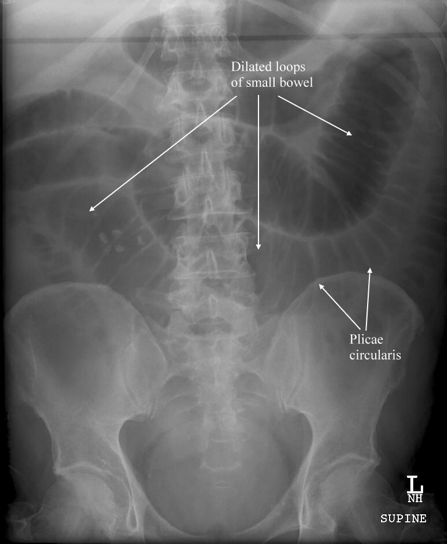

- Plain Radiographs

- Special Considerations on Radiography